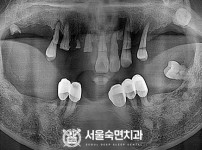

상악동거상술, 뼈이식 / 숙면임플란트 12개 - 오스템임플란트 (김*현님)

해당 게시물은 의료법 제56조에 의거하여 로그인 후 열람이 가능합니다.

구분 임플란트